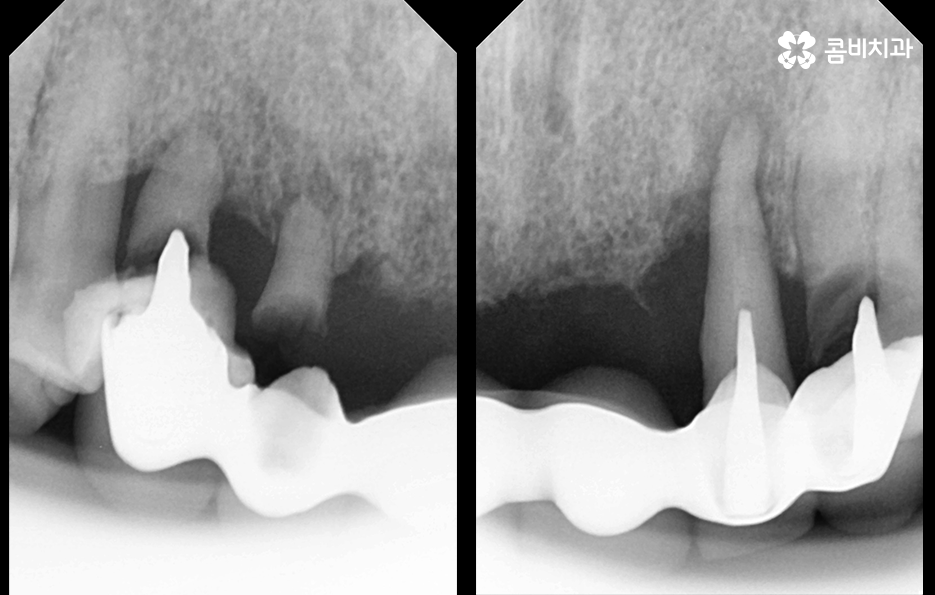

오늘 포스팅의 사례의 경우 앞니를 이미 잃은 상태였지만 주변 치아를 활용하여 브릿지로 연결해놓은 상태에서 기존의 치아가 버티지 못하여 앞니임플란트 하게 된 경우라고 볼 수 있는데요.

아무래도 잇몸이 내려앉게 될 경우 임플란트의 보철물이 길어 보이게 될 수 있고 잇몸은 한번 내려 앉으면 회복이 어렵기 때문에 초기에 잇몸을 최대한 보존하면서 치료하는 것이 중요한 거예요.

잇몸 상태와 전신 건강이 양호한 경우에는 원데이임플란트를 통해 앞니임플란트 치료를 많이 진행하지만 오늘 케이스처럼 이미 치아를 발치한 후 시간이 지난 경우나 치주염으로 인해 잇몸 뼈가 녹고 염증이 심한 경우에는 빠른 치료보다는 잇몸을 충분히 회복하여 건강하고 안전한 결과에 더 초점을 두고 있는데요.